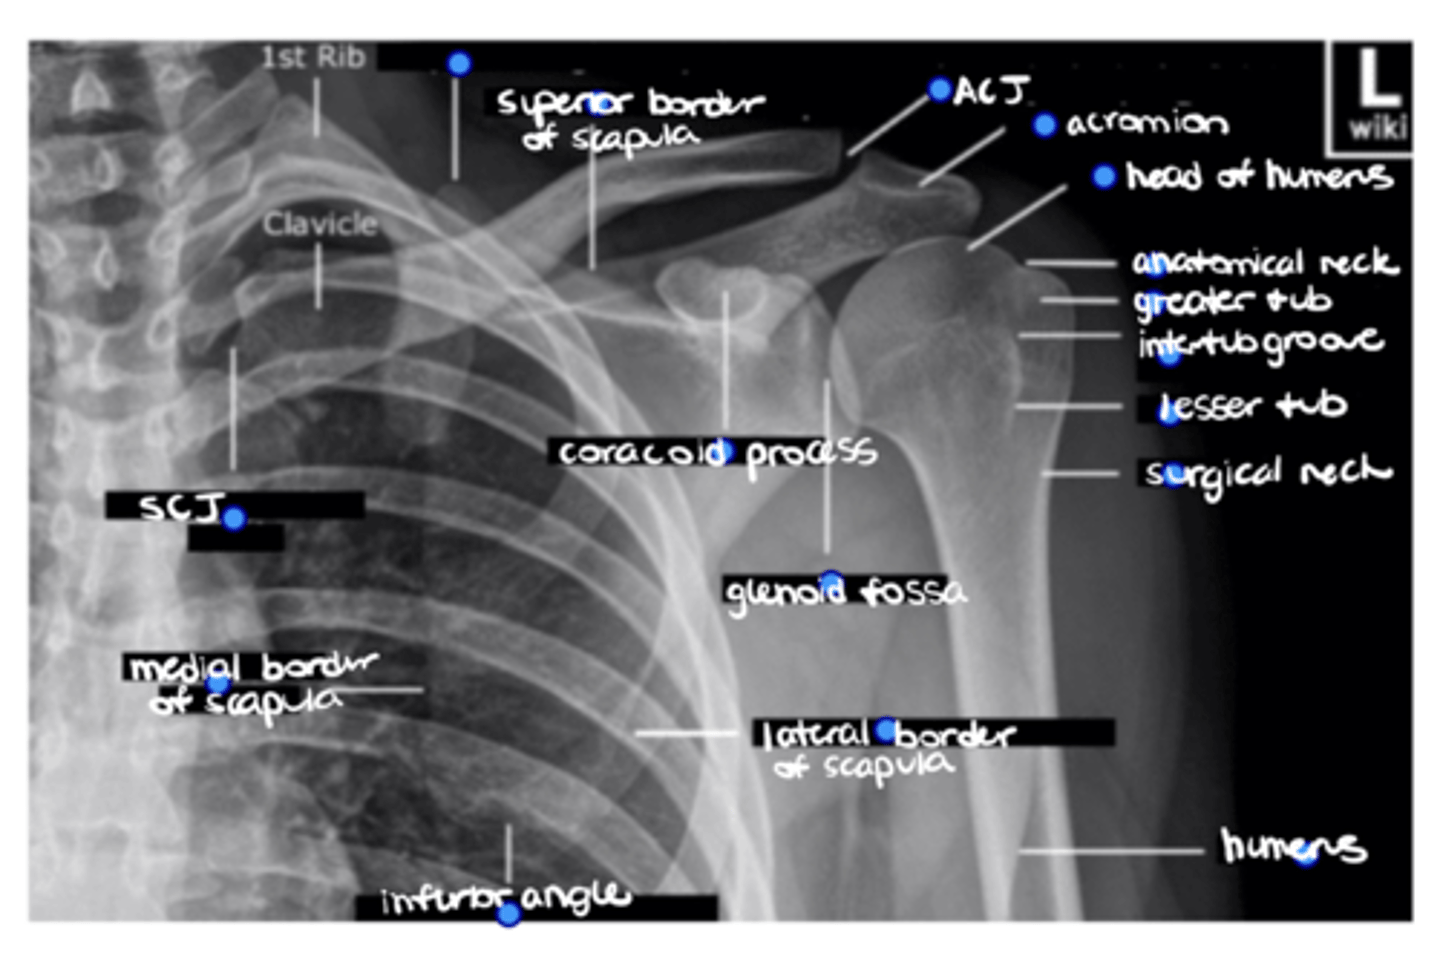

Superior angle of the scapula

ID the missing structure.

Superior border of the scapula

ACJ

Acromion

1. Head of humerus

2. Anatomical neck

3. Greater tuberosity

4. Intertubercular groove

5. Lesser tuberosity

6. Surgical neck

ID the 6 missing structures.

Shaft of the humerus

1. Coracoid process

2. Glenoid fossa

ID the 2 missing structures.

1. Lateral border of the scapula

2. Inferior angle of the scapula

3. Medial border of the scapula

ID the 3 missing structures.

SCJ